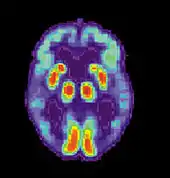

La maladie d'Alzheimer (MA) est une maladie cérébrale progressive, dégénérative et fatale, dans laquelle est recensée une perte importante des cellules. Par conséquent, la mort des cellules cérébrales survient, bien que cette maladie soit la forme de démence la plus répandue[10]. À travers le monde, il existe 1 à 5 % de la population atteinte de la maladie d'Alzheimer[11]. Il est estimé que 500 000 Canadiens souffrent actuellement de la maladie d'Alzheimer ou d'une autre démence liée. Elle est la cause de handicap la plus répandue chez les individus âgés de 65 ans ou plus[10]. Les femmes sont disproportionnellement atteintes par cette maladie[12].

Scan par TEP d'un cerveau en bonne santé.

Scan par TEP atteint de la MA.